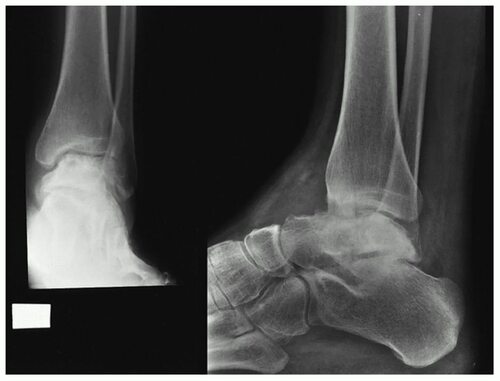

Артроз голеностопного сустава – это хроническое дегенеративное заболевание, которое поражает суставную поверхность голени и стопы. Оно характеризуется разрушением хрящевой ткани, что приводит к болезненности и ограничению движений.

В данной статье представлены многочисленные фотографии, иллюстрирующие процесс лечения артроза голеностопного сустава. Они помогут вам визуализировать методы лечения и понять, какие изменения происходят в суставе в процессе реабилитации.